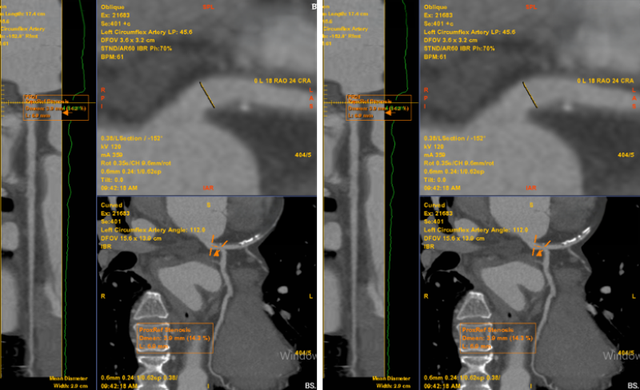

Nhận định cơn đau ngực có nhiều khả năng liên quan đến bệnh lý mạch vành, các bác sĩ đã chỉ định chụp MSCT mạch vành. Kết quả cho thấy bệnh nhân có mảng xơ vữa hỗn hợp gây hẹp khoảng 60–70% đoạn LAD1–2, được phân loại CAD-RADS 3.

Chỉ đau tức ngực trái thoáng qua, không ngờ phát hiện bệnh lý tim mạch nguy hiểm- Ảnh 1.

Bất thường được phát hiện trên phim chụp MSCT mạch vành của bệnh nhân (Ảnh: Medlatec).